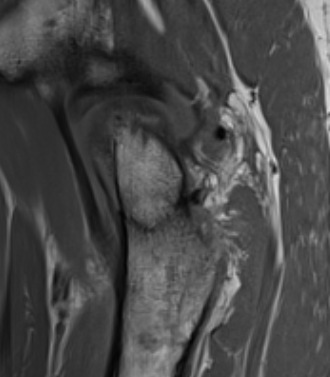

Coxa vara / coxa valgus

? FAI

Femoral neck fracture on right in patient with coxa vara